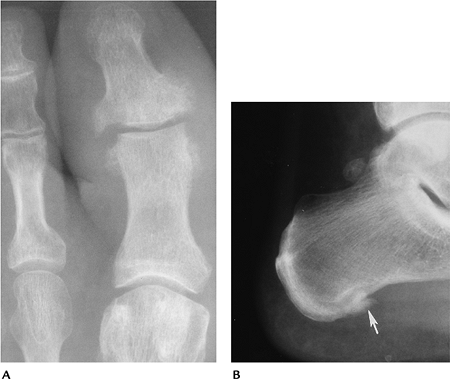

![]() |

FIGURE 6-74 (A) Sausage digit in Reiter syndrome. Characteristic diffuse swelling with erosions and proliferation of the distal joint. (B) Poorly defined spur (arrow) and swelling at the plantar aspect of the calcaneus caused by Reiter syndrome.